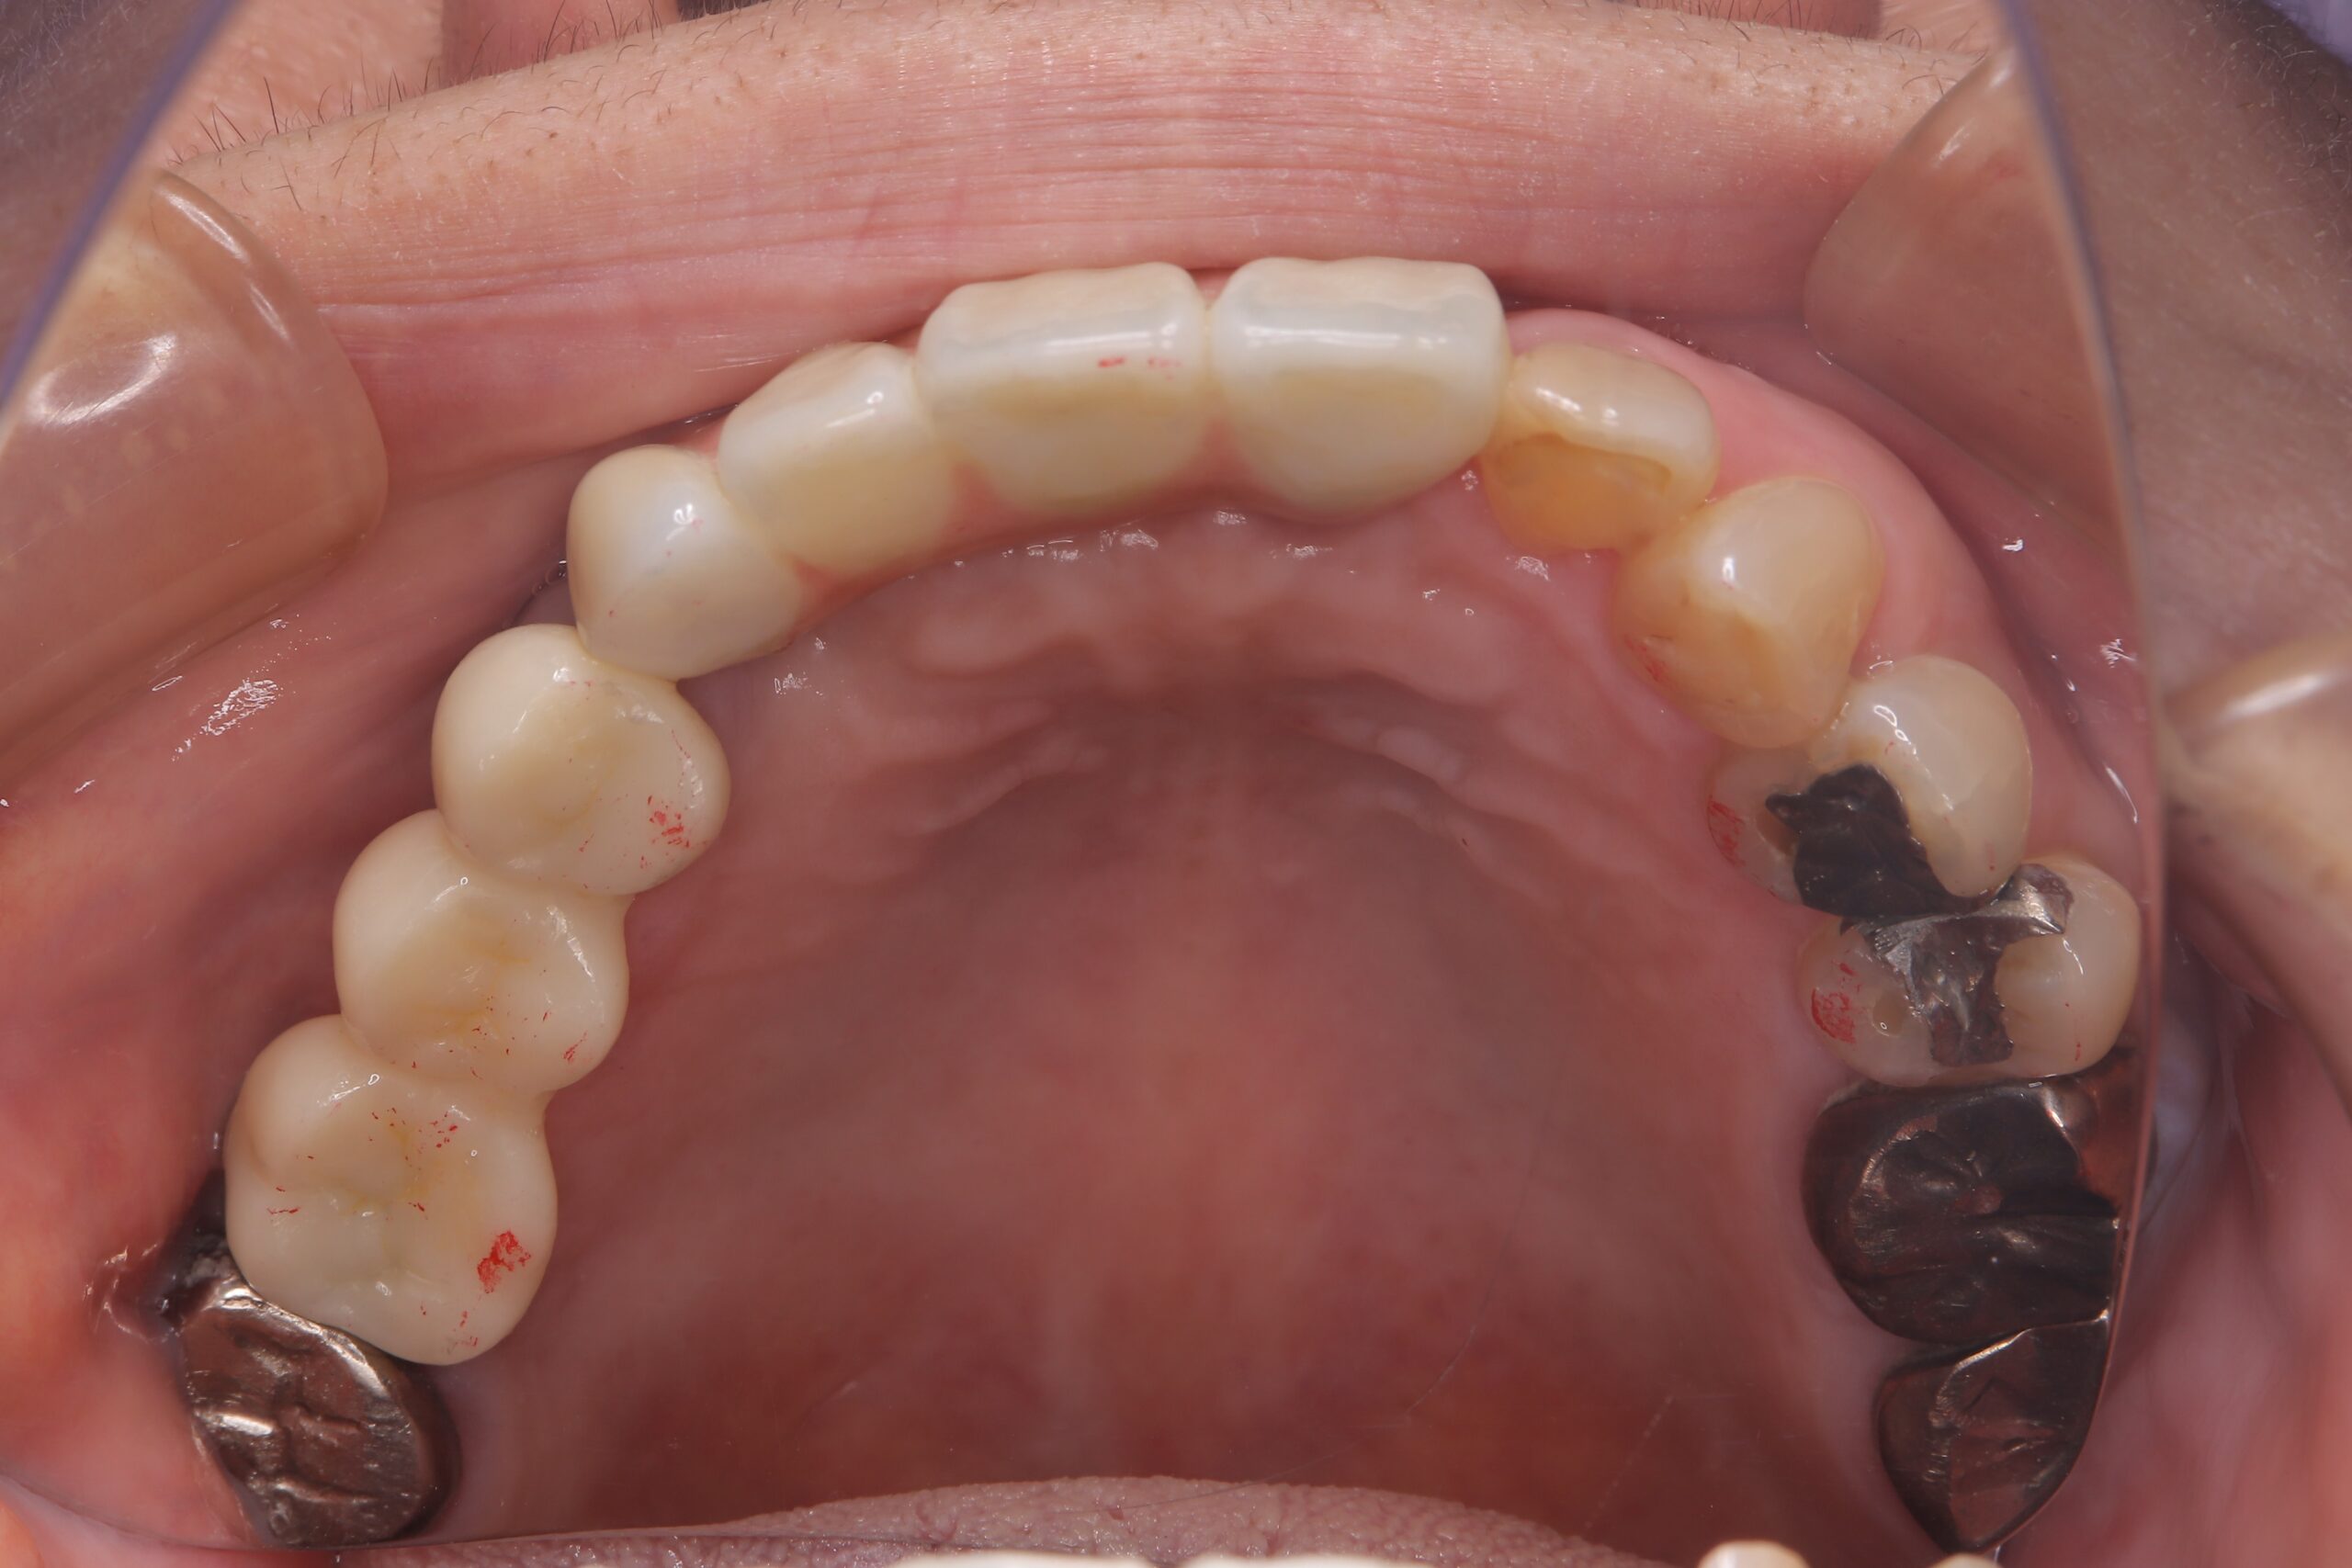

治療後

咬合面観

入れ歯ではなく、前歯だけインプラントにする選択肢も悪くないと思います。